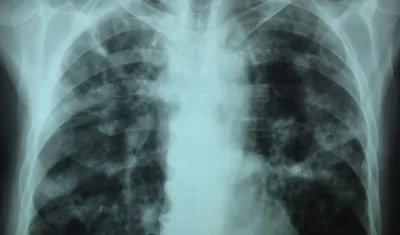

Imagen de referencia.

Colombia es el quinto país de la región con mayor carga de casos de tuberculosis.

Los reclusos aportan el 7,0% de la notificación de tuberculosis en Colombia.

La enfermedad es causada por la bacteria "Mycobacterium tuberculosis", que casi siempre afecta a los pulmones.